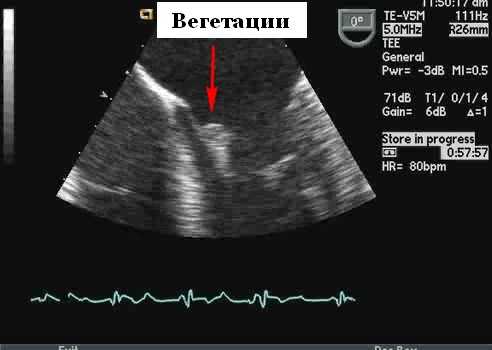

Вегетации из-за инфекционного эндокардита являются потенциально важными источниками эмболии, поэтому при подозрении необходимо проводить эхокардиографию. Как правило, у пациента в анамнезе есть рецидивирующая лихорадка и конституциональные симптомы, а также возможный провоцирующий фактор (недавняя стоматологическая или другая инвазивная процедура). Первичная идентификация вегетаций во время оценки потенциального источника эмболии становиться вероятной, поскольку диагноз обычно подозревается клинически. Таким образом, большая часть вегетаций выявляется на эхокардиографии до того, как возникают серьезные эмболические осложнения.

Эхокардиографические особенности при инфекционном эндокардите

Вегетации имеют ряд типичных эхокардиографических характеристик, и диагноз обычно может быть установлен с относительно высокой степенью уверенности с помощью эхокардиографии в сочетании с клинической симптоматикой. Они кажутся менее отражающими (серыми) по сравнению с нормальной тканью клапана и расположены перед клапаном на линии струи регургитации (предсердная поверхность митрального клапана и поверхность желудочков створок аорты). Обычно они выглядят дольчатыми с неровными, плохо очерченными границами и имеют хаотическое движение, в отличие от других клапанных образований (фиброэластомы и т. д.), которые имеют тенденцию к более высокому отражению, с четко определенными границами и менее хаотичным движением. Тонкие протяженные клапанные прикрепления с узким основанием, скорее всего, будут неинфекционными фибринозными нитями, чем вегетациями. Признаки, которые помогают отличить вегетации от других образований, включают наличие разрушения створки, регургитации клапана и образования абсцесса или свища. Сообщается, что чувствительность трансторакальной эхокардиографии для выявления признаков эндокардита составляет от 44 до 60%, по сравнению с чувствительностью 88 и 100% для ЧПЭхоКГ. Мелкие вегетации ( 90%), хотя при более высоком разрешении чреспищеводной эхокардиографии повышенная чувствительность может происходить за счет немного сниженной специфичности (возможность маркировать небольшие доброкачественные фибринозные тяжи на нативных и протезных клапанах или незначительно подвижные шовный материал на протезах клапанов в виде мелких нитей).

Риск эмболизации, связанной с вегетацией, варьируется в широких пределах (17-50%). Факторы, связанные с риском эмболии, включают их размер, подвижность и временные изменения размера вегетаций. Наиболее важным эхокардиографическим признаком, который позволяет прогнозировать риск эмболии, является размер вегетации. Если они размером> 10 мм, то имеют значительно более высокую частоту эмболических событий по сравнению с более мелкими вегетациями (47% против 19%). Увеличение или отсутствие изменений вегетации после 4-8 недель терапии связано с увеличением частоты эмболических событий (45% против 17%). Вегетации на митральном клапане имеют более высокий риск эмболии. Некоторые микроорганизмы связаны с образованием более крупных вегетаций, включая Staphylococcus aureus и группу организмов HACEK. Несмотря на адекватную антибактериальную терапию, вегетации могут стать организованными и сохраняться, и эти остаточные поражения с гораздо меньшей вероятностью будут давать эмболию.

Протезы клапанов на эхокардиографии

Предполагается, что эмболическое событие у пациента после протезирования клапана связано с протезом, пока не будет доказано обратное. Источником эмбола может быть тромбоз клапана, клапанные вегетации или тромб левого предсердия (при митральном протезе). В одной серии пациентов с протезами клапанов, перенесших чреспищеводную эхокардиографию для исследования потенциального источника эмбола, тромб был обнаружен на клапане примерно в 25% случаев. Для механических протезов общая частота тромбоэмболии составляет 0,7-1% на пациента в год для тех, кто лечится антикоагулянтами - гораздо более низкий уровень (4% на пациента в год), чем у тех, кто не использует антикоагулянты. Относительный риск эмболии выше при протезах митрального клапана, чем при протезах аорты, что, скорее всего, связано с более низкой скоростью потока через митральный клапан. Чреспищеводная эхокардиография более предпочтительное исследование для оценки протезов механических клапанов. Из-за акустического затенения поверхность со стороны ЛП не может быть хорошо видна с помощью трансторакального доступа, а протезы аорты обычно лучше видны из чреспищеводного доступа. Вегетации или тромбы на этих клапанах могут выглядеть одинаково, хотя вегетации обычно связаны с конституциональными симптомами и возможной периклапанной регургитацией или частичным раскрытием клапана. Тромб обычно возникает при неадекватной антикоагуляции. Обычно тромб является подвижным на створках клапана и клапанном кольце, связан с эффектом спонтанного эхоконтрастирования и может вызывать обструкцию клапана с повышенным допплеровским градиентом.